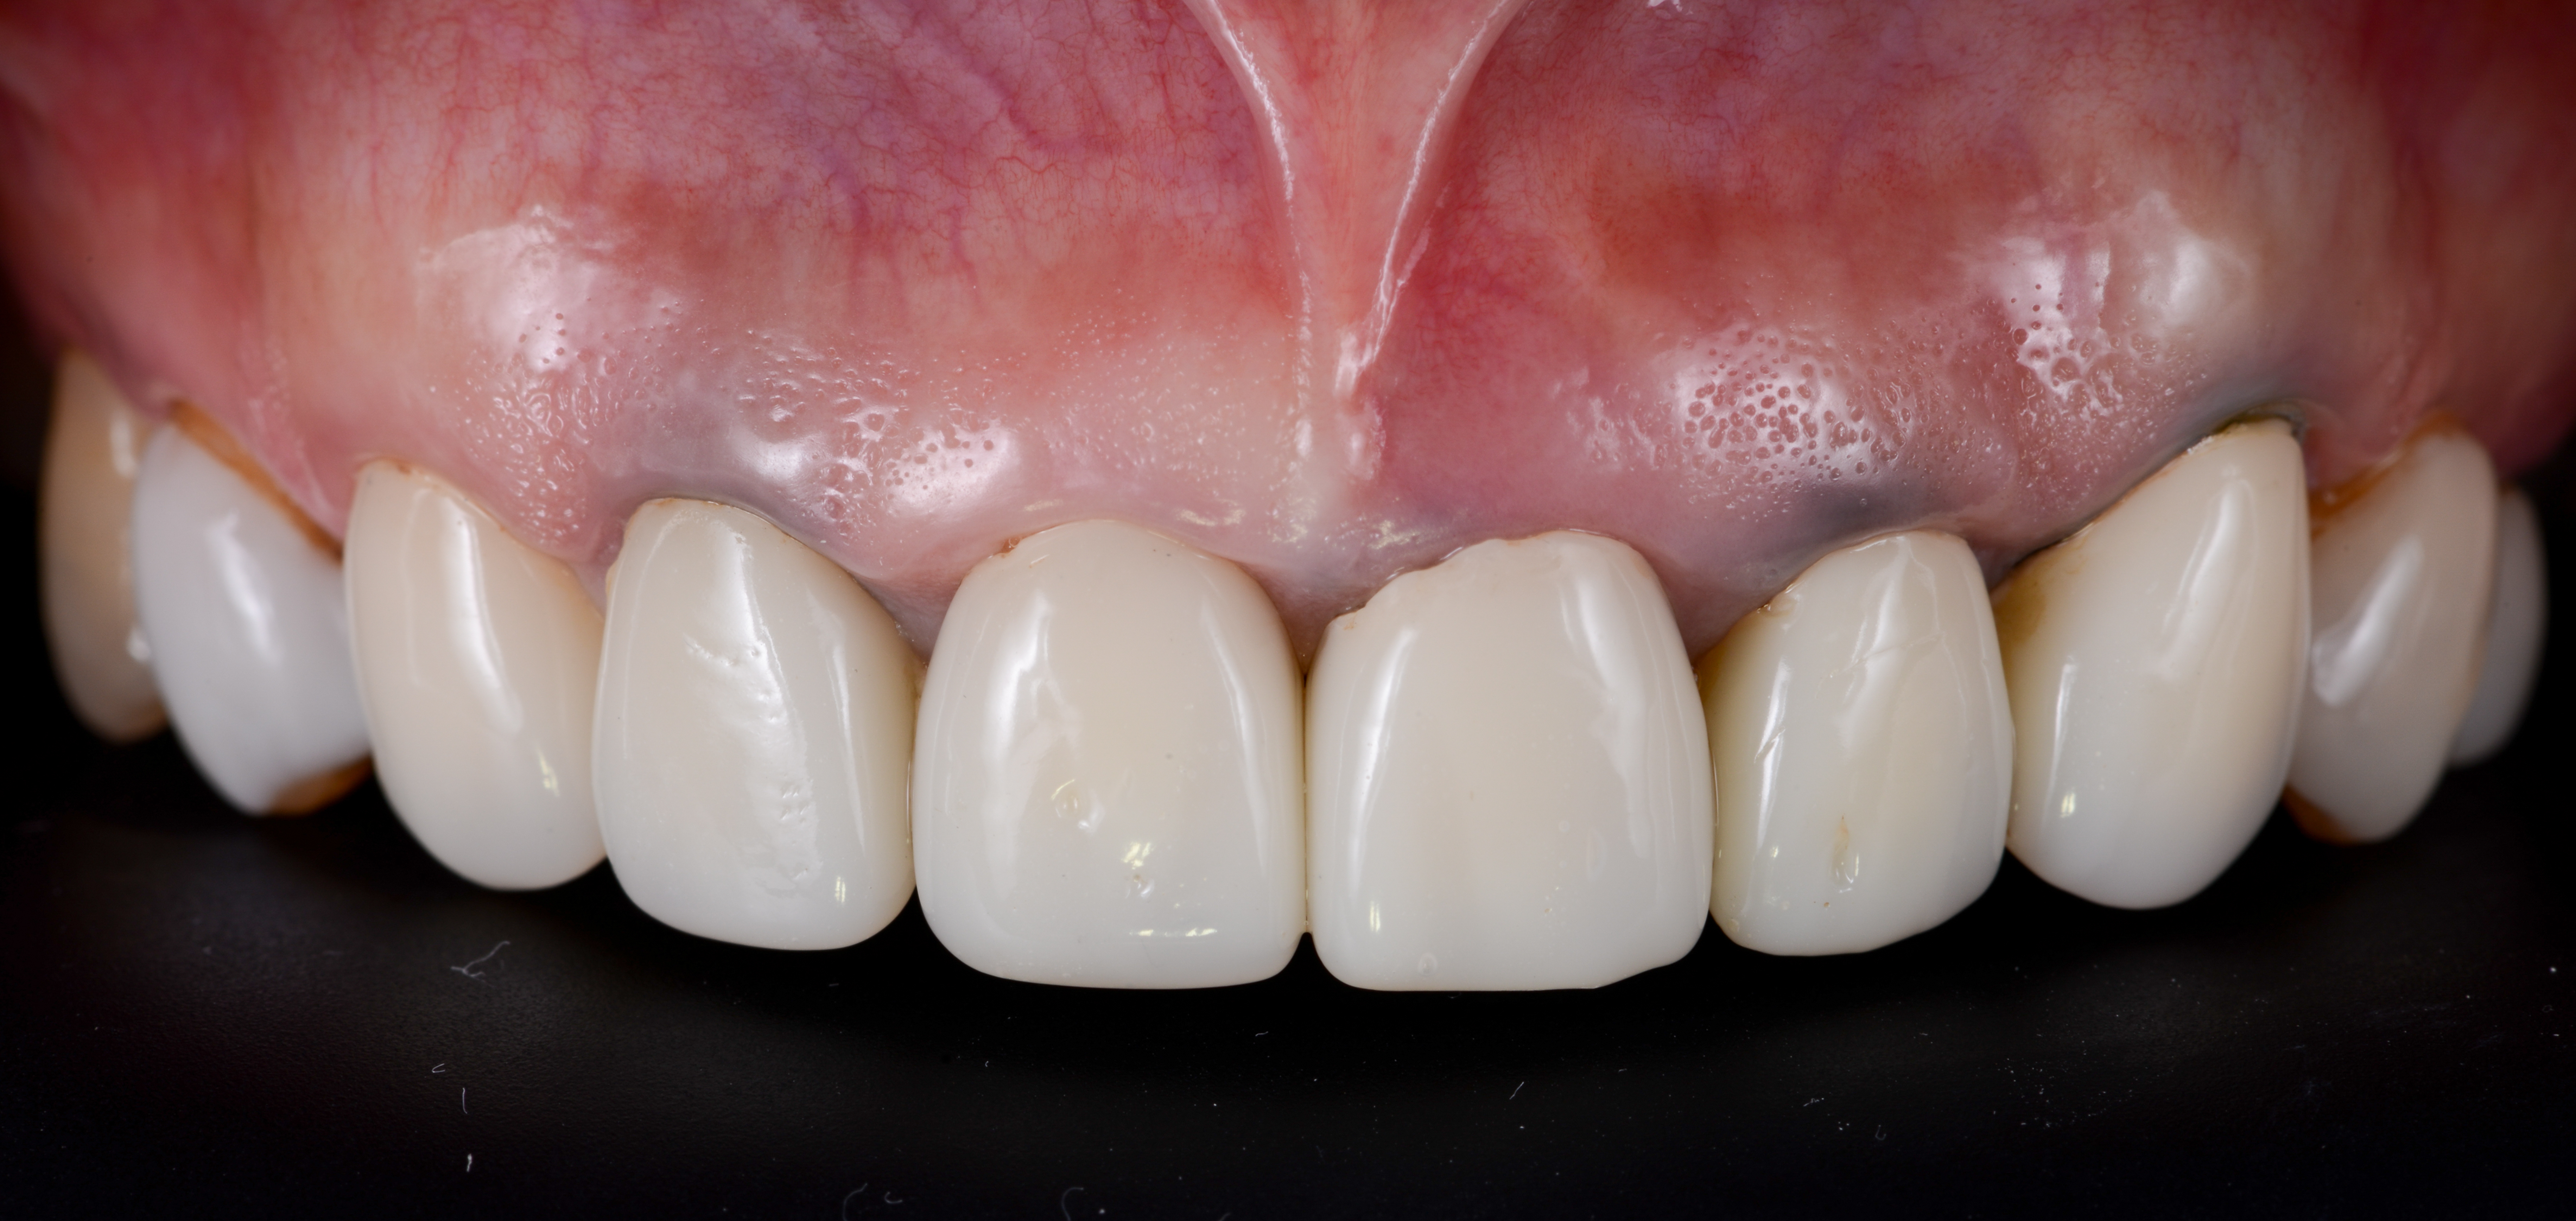

ガミースマイルを歯周形成外科で改善し、笑顔を取り戻した症例

- 年代、性別 30代・女性

- 来院動機 ガミースマイルを治したい

- 治療内容 歯周形成外科

ガミースマイルを歯周形成外科で改善した症例

- 年代、性別 27歳・女性